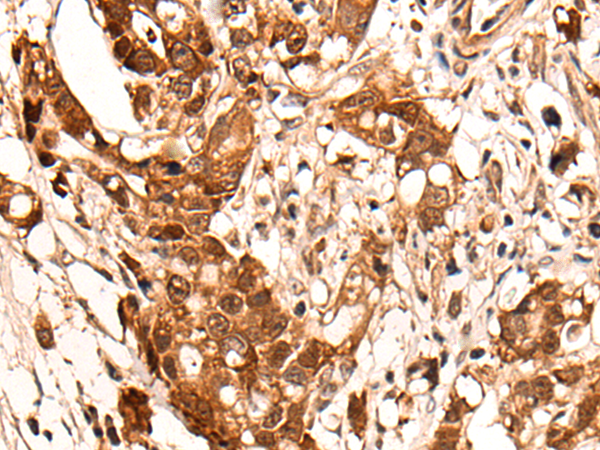

IHC positive control: |

Human ovarian cancer and human gastric cancer |